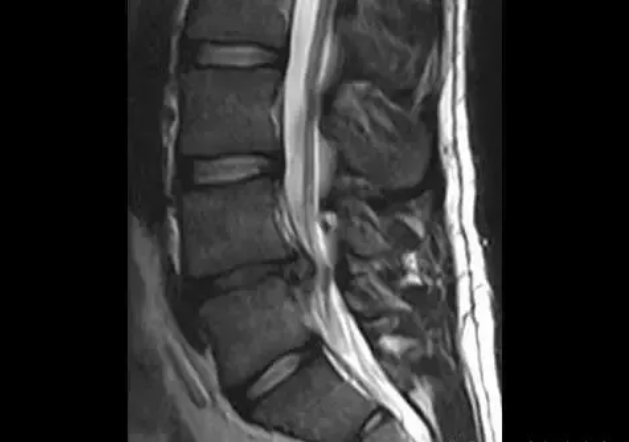

图中发黑部分的那一段椎间盘就是退变的椎间盘且正在突出。

这是在腰椎MRI里我们可以看到的竖脊肌

虽然MRI是平躺中检查的,肌肉截面积大小不足以证明肌肉力量和弹性,但是有经验的医生还是可以通过两侧肌肉的灰度和大小来推测病人日常活动的习惯。